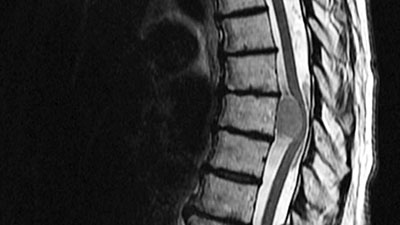

تومور نخاعی